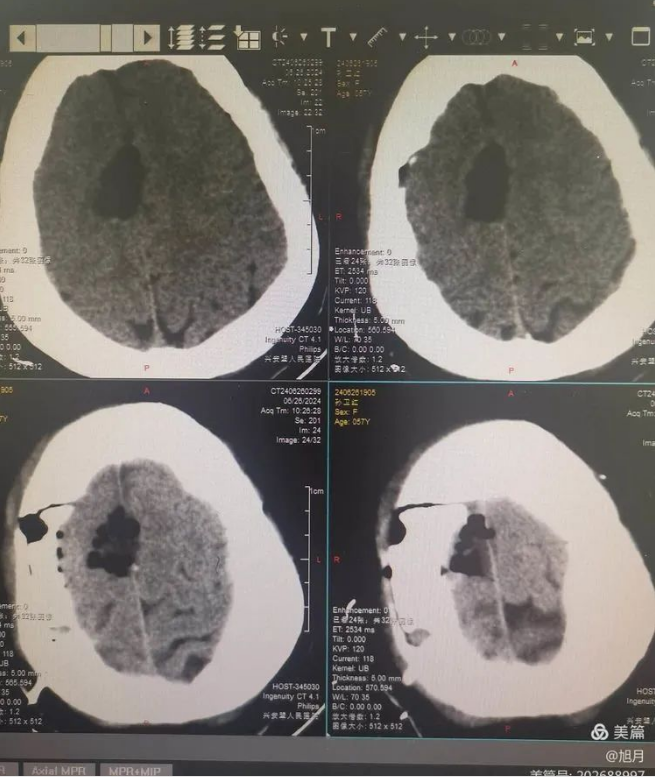

术后复查

术后复苏后患者神清语明,四肢活动自如,头痛好转。头部切口愈合良好,无红肿渗出及皮下积液等。